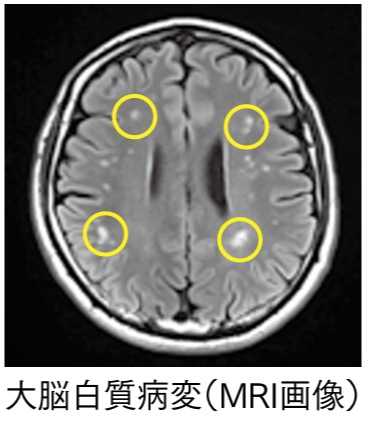

特に認知症や脳梗塞の脳での大きな特徴は、脳の萎縮と白質病変です。これらはそれ自体は病気ではないのですが、認知症になる前にいきなり萎縮が起きるのではなく、何十年もかかって進行していきます。その間にしっかりと脳の状態を観察でき、予防行動の動機にしていただけると考えています。

高橋院長:なるほどです。私の専門分野は循環器ですが、人間ドックの結果説明において、診断結果は全身に関することになるので、脳ももちろんその中に入るわけです。その中で白質病変という言葉が結構出てきます。ただ、ご高齢の方でも白質病変があまりない方と結構ある方がいらっしゃいます。

脳ドックプロジェクトでは、40歳以上の人の脳の萎縮は実は30歳くらいから始まるのですが、40歳を超えた辺りから標準の領域から大きく外れてしまう人が結構多くいることに気づきました。しかし誰にも起きる変化ですから、脳の萎縮と白質病変自体は病気ではなく、過度でない限り医療の対象にはなりません。せっかく脳ドックでMRIを撮っても、読影では記述されないこともあります。

最初の「自分の脳の状態を知ること(測る)」ためには観察が必要です。私たちは、例えば鏡を見るとか体温計で体温を測る。あるいは年に一度の健康診断で様々な臓器の機能を測ります。すなわち、健康管理の第一歩は観察です。そこではきちんと数値を測り経年変化を観察するということが基本です。脳の健康も全く一緒です。しかし脳はとても頑健に外から守られているため、その情報はなかなか外に漏れ出てきません。その中で、多少高価な検査になりますが、脳の状態を直接観察できるMRIは、最も効果的な観察方法です。そして冒頭に述べたように、MRIで観察できる脳の萎縮と白質病変が、脳の二大健康指標であると私は考えています。

また、現在のMRIによる検査対象は、重篤な病気を見つけるための「二次予防」と呼ばれる早期発見で、まだ病気がない人、血圧で言えば90が100になり、100が110になりという医療の対象以前に、徐々に悪化するのを数値で把握するというものではありません。そこをエムビジョン・ヘルスで健常な時からしっかりと数値を基に脳の2大健康指標である脳の萎縮と白質病変をモニタリングしていくことが重要です。

2番目は「リスクを正確に理解すること(知る)」です。リスクとは、今まだ起きていないが将来に起きるかもしれないことに対する考え方です。今まだ健康な皆様に、「将来この病気になります」という予言をすることは、認知症や脳梗塞に限らず、心臓病でもがんでも、ほとんどの病気で不可能です。ですから、萎縮や白質病変があれば「必ずこの病気になります」ということではありません。ただ、認知症や脳梗塞になったか人の脳を調べてみると、萎縮や白質病変が多いというのがよく見られる特徴です。実際に私たちの研究でも、萎縮の大きい人の方が、5年10年後に軽度認知症を発症する頻度が高いという結果が得られています。その一方で、萎縮が非常に少ない人には認知症の人が非常に少ないという結果が得られています。

このようなエビデンスを統合すると、脳萎縮や白質病変も将来の脳の健康リスクであることが言えます。繰り返しますが、脳萎縮や白質病変は過度でない限り、それ自体脳の病気と診断されるものではありません。萎縮と白質病変の程度は、自分の脳の健康状態の大切な指標の一つとしてとらえてください。